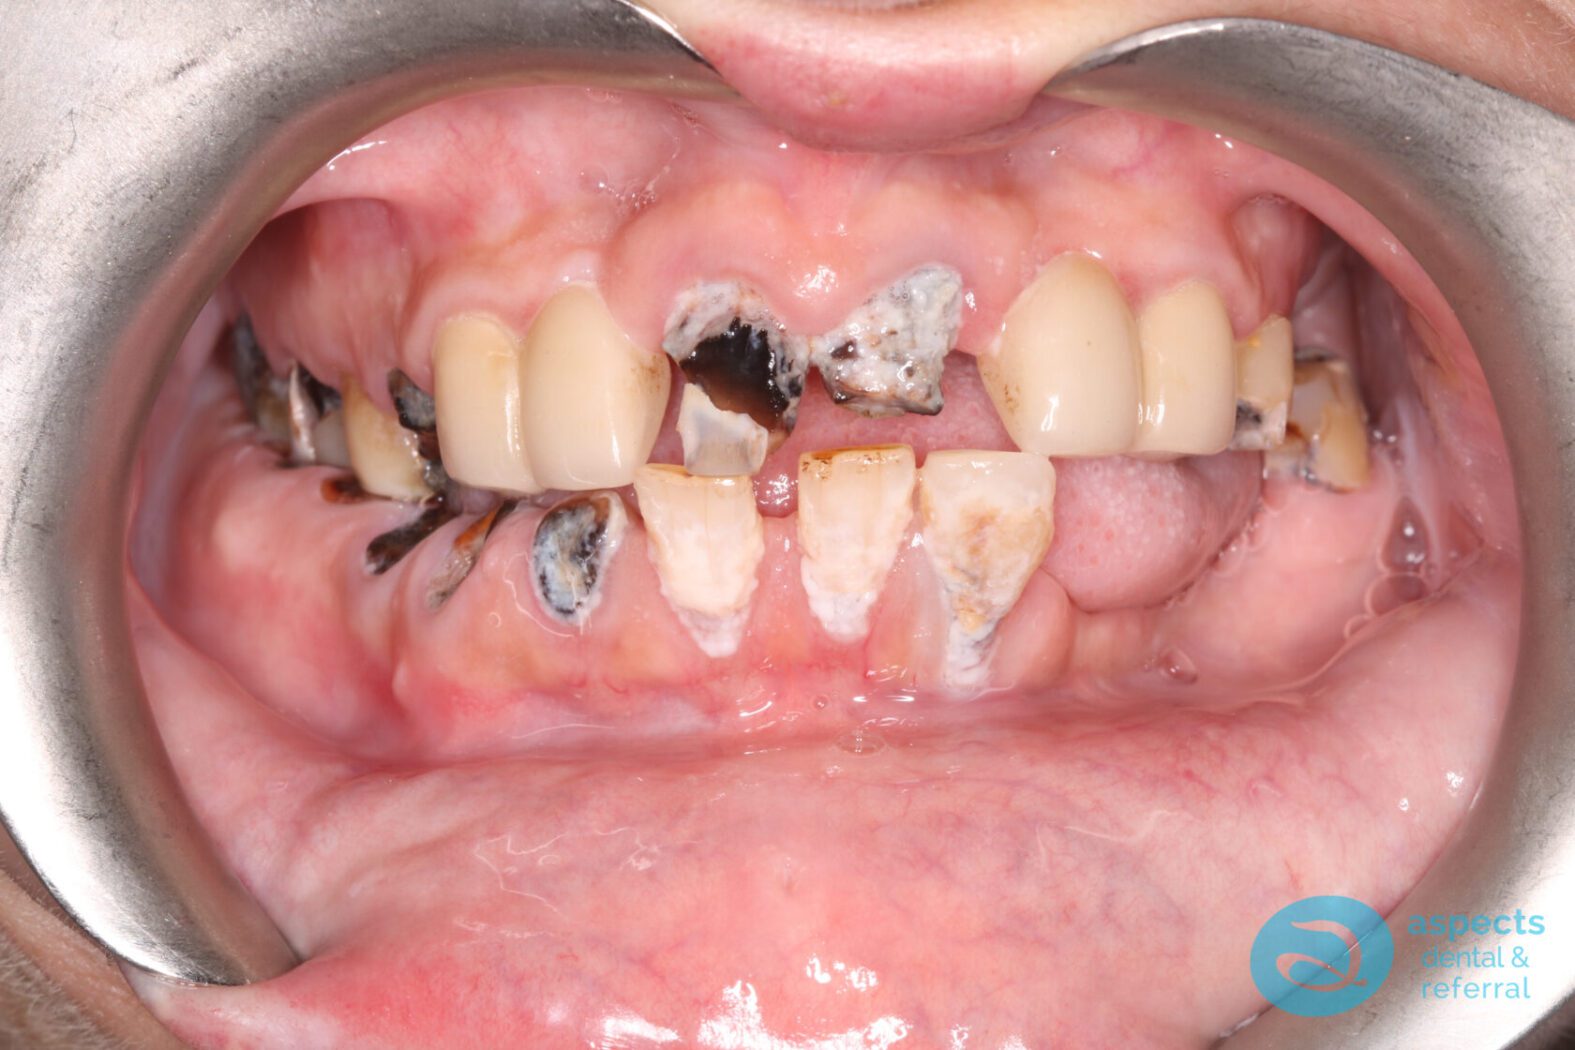

Our Dental Patient initially presented with neglected dentition, with the majority of teeth deemed non-restorable due to extensive decay and/or Periodontal Disease. Comprehensive treatment planning was carried out, and it was determined that full-mouth extractions were necessary.

Before Implant-Retained Overdentures Photo